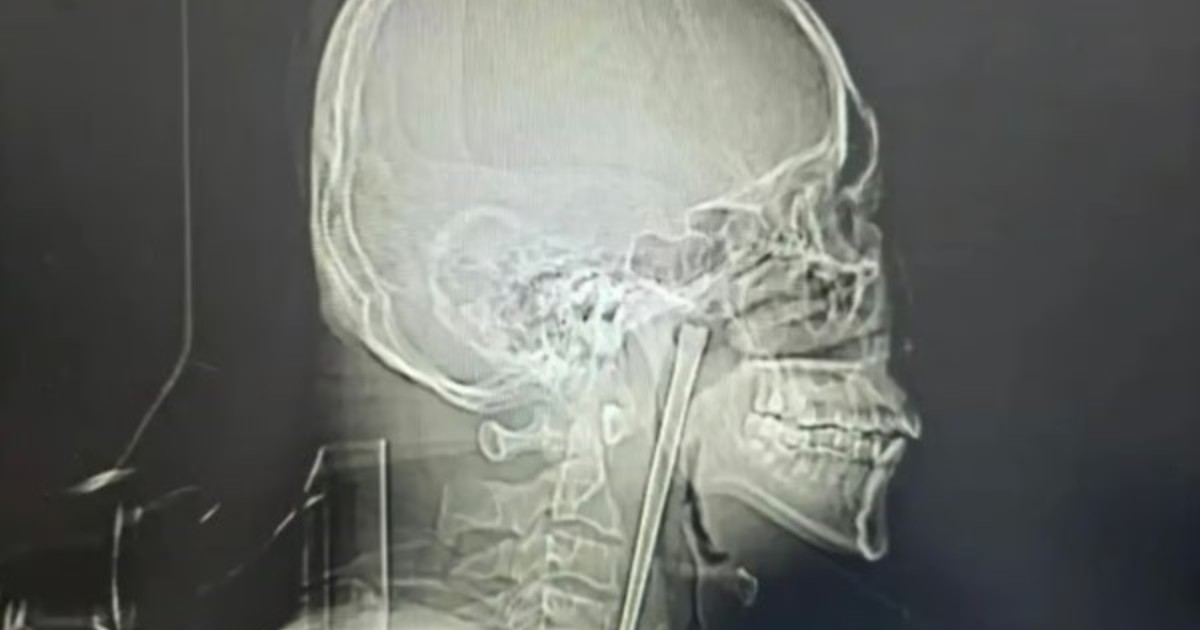

Un hombre vivió 8 años con un palillo de metal atascado en la garganta

El palillo medía 12 centímetros de largo.Tras una operación exitosa le fue retirado....